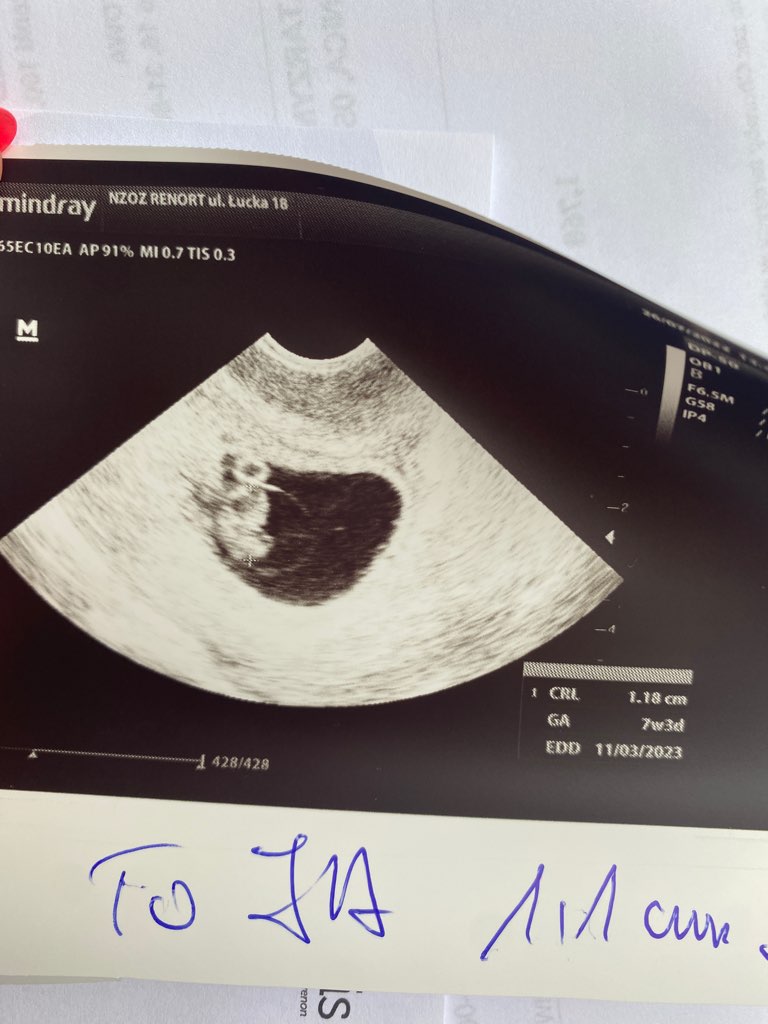

Dziewczyny ja już po pierwszym USG :D spadł mi kamień z serca. Dzidzia około 8 tygodni, serduszko bije. Wszystko wygląda tak jak powinno <3 Odnośnie plamień to dowiedziałam się, że na początku ciąży bardzo często się zdarzają. Jeśli jest to malutka ilość i nie ma przy tym bólu brzucha to nie jest powód do niepokoju. Mam trochę za niskie ciśnienie, ale będziemy to monitorować. Kolejne USG za 3 tygodnie. Jak zobaczyłam maleństwo na ekranie to nie mogłam powstrzymać łez. Miłość od pierwszego wejrzenia :)